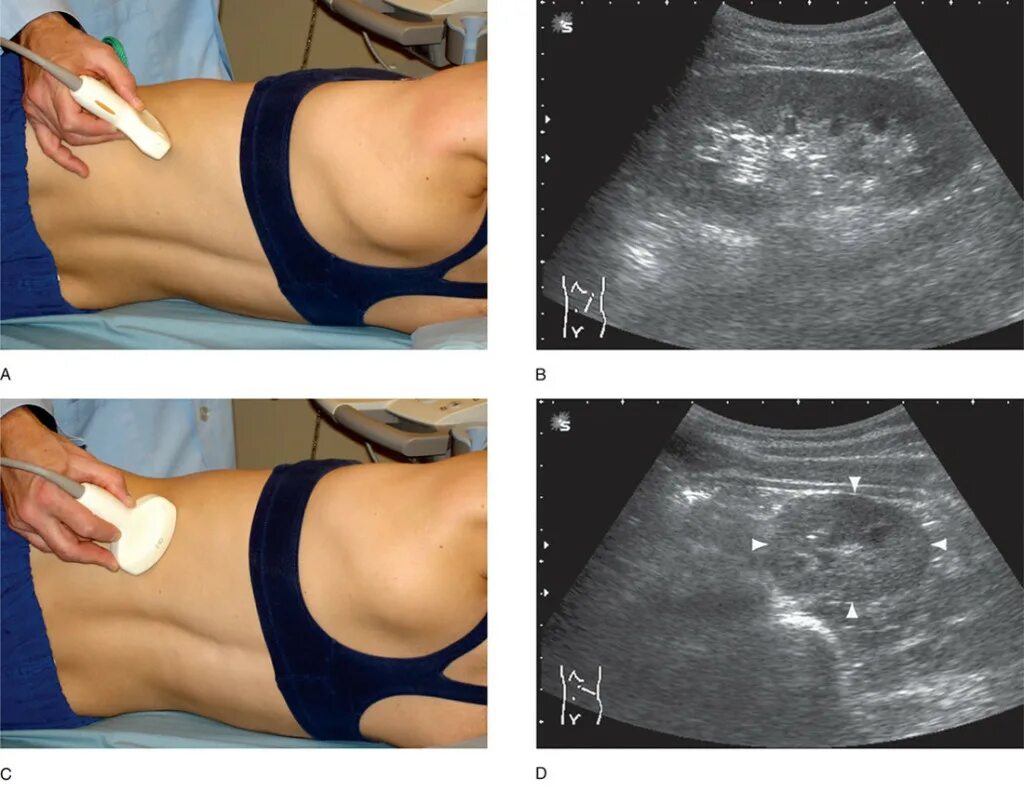

Узи надпочечников и забрюшинного пространства подготовка